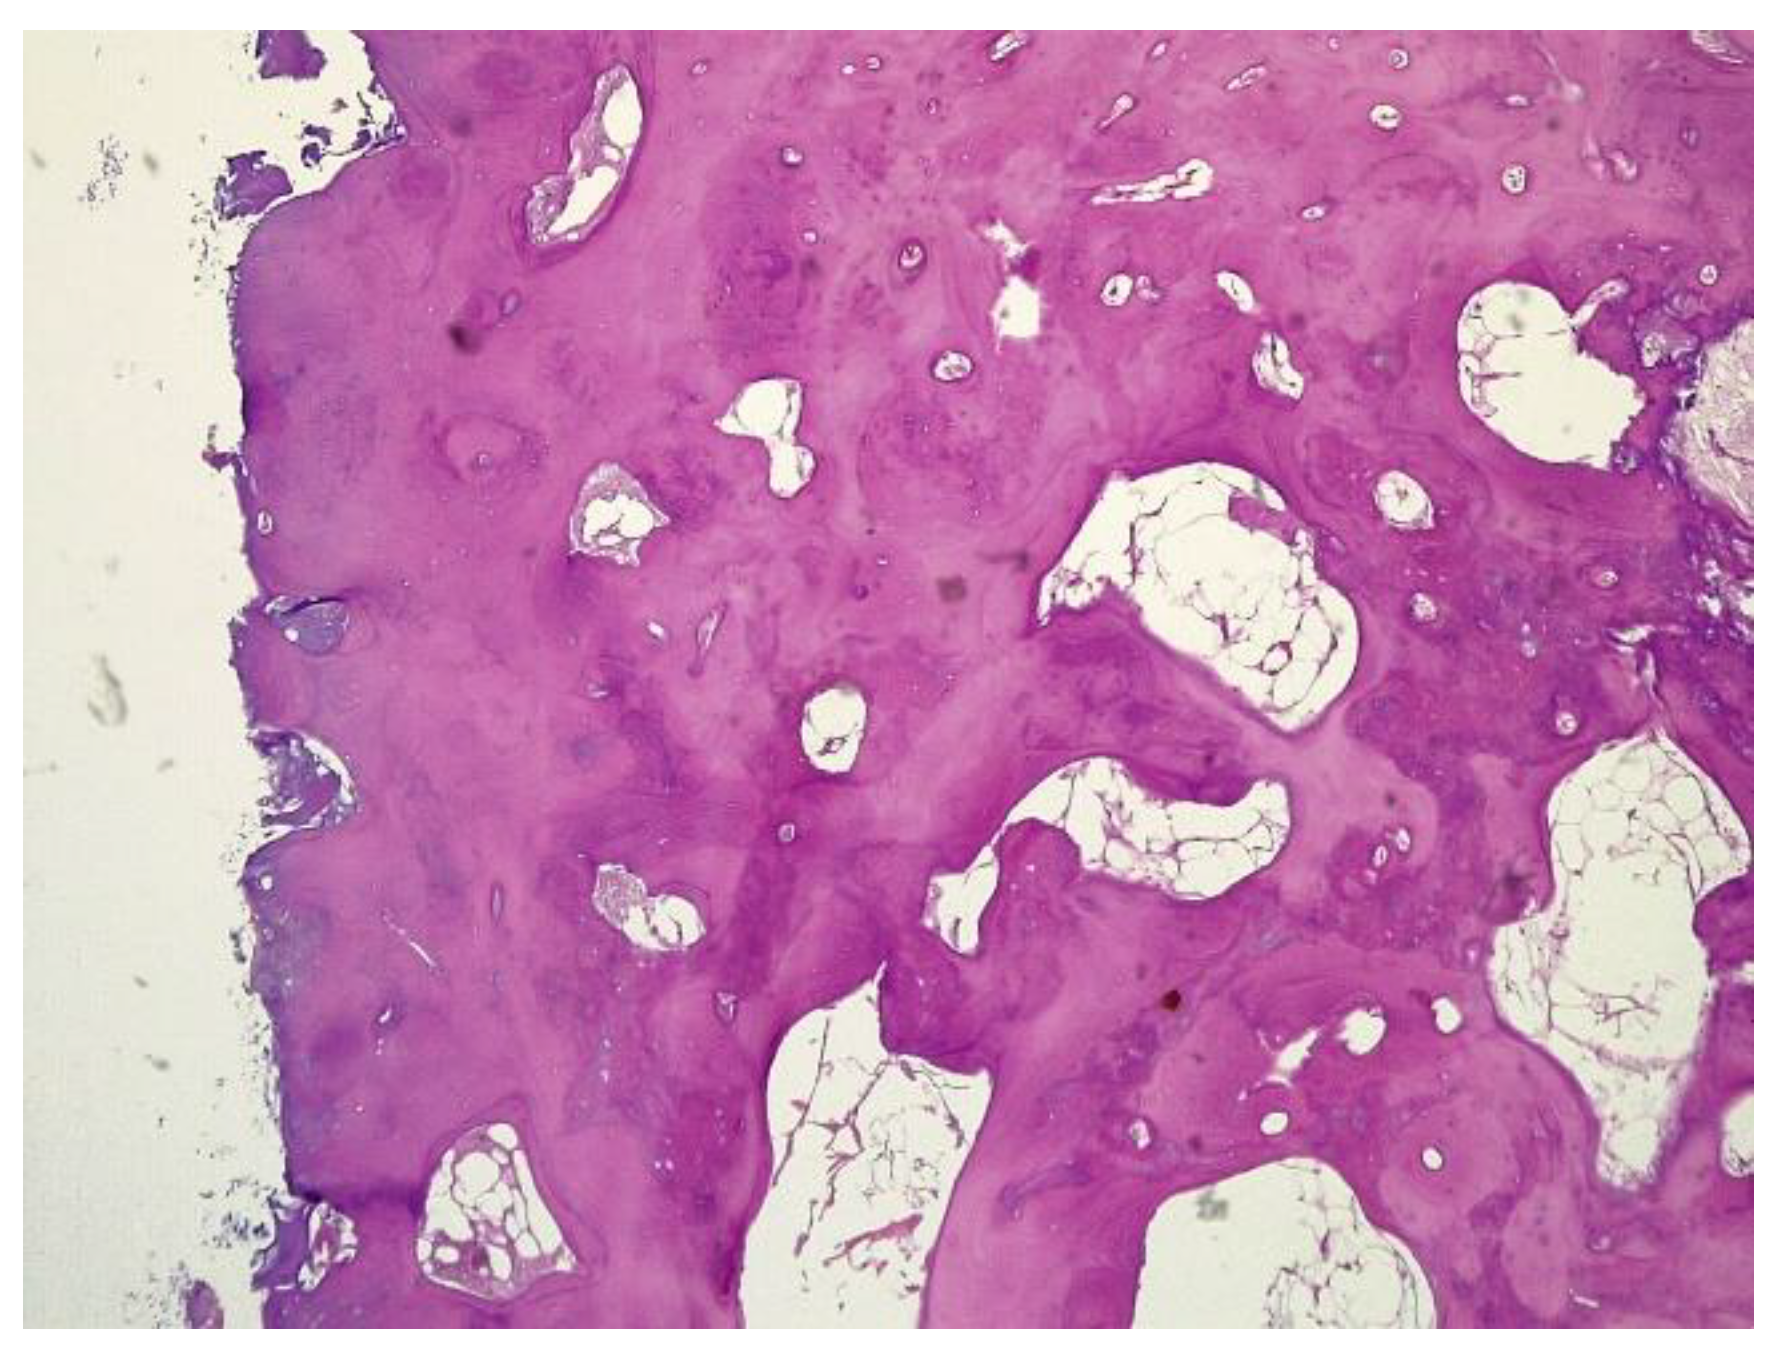

The histopathological result supported the diagnosis of melorheostosis (Figure 5, Figure 6, Figure 7 and Figure 8). Additionally, immunohistochemical tests completed the data obtained after the microscopic examination through the classic histopathological technique. CD45/LCA (clone PD7/26/16 and 2B11, Biocare) demonstrated the presence of inflammatory cells, but overall, the rest of the immunohistochemical tests were non-specific and did not reveal the presence of epithelial or other tumor proliferations on the analyzed specimens. CD138 (clone B-A38, Biocare) showed rare plasma cells dispersed in hematoforming marrow, CD56 (clone BC56C04, Biocare) highlighted few osteoblasts, and all specific immunomarkers for cytokeratins were negative (Pan Cytokeratin AE1/AE3 clone AE1/AE3 and CK8/18 clone CK8/18 both from Biocare). Ki67 (clone SP6, Biocare) was negative in areas of reactive fibrosis and positive in a few cells in the hematoform marrow, suggesting a benign lesion. CD56 usually highlights neuroendocrine tumors, myeloma, myeloid leukemia, and Nk/T cell lymphomas and is also positive in some rare sarcomas. The negative panCK marker denied the possible epithelial tumor origin. Although there are no specific immunomarkers for this pathological entity, there are some studies that try to find correlations between the immunohistochemical expression of some proteins and the severity of the lesions. One study used immunohistochemistry to investigate the expression of several proteins in the affected bone tissues of melorheostosis patients. The study found that there was increased expression of certain proteins, including transforming growth factor beta (TGF-β), bone morphogenetic protein 2 (BMP-2), and insulin-like growth factor 1 (IGF-1) in the bone tissues of melorheostosis patients compared to healthy controls [8].

The histopathological appearance varies, but several pathognomonic changes have been identified, such as increased bone cortical density, the presence of woven bone features, hypervascular features, an increased number of Haversian systems, and irregular bone growth into the medullary cavity; moreover, newly deposited unmineralized osteoids were seen in affected lesions [23].

Figure 5. Marked endosteal sclerosis with marrow fibrosis.

Figure 6. Abnormal proliferation of thickened compact, haversian, or woven bone distorting the normal smooth contour of the periosteal surface of the bone.